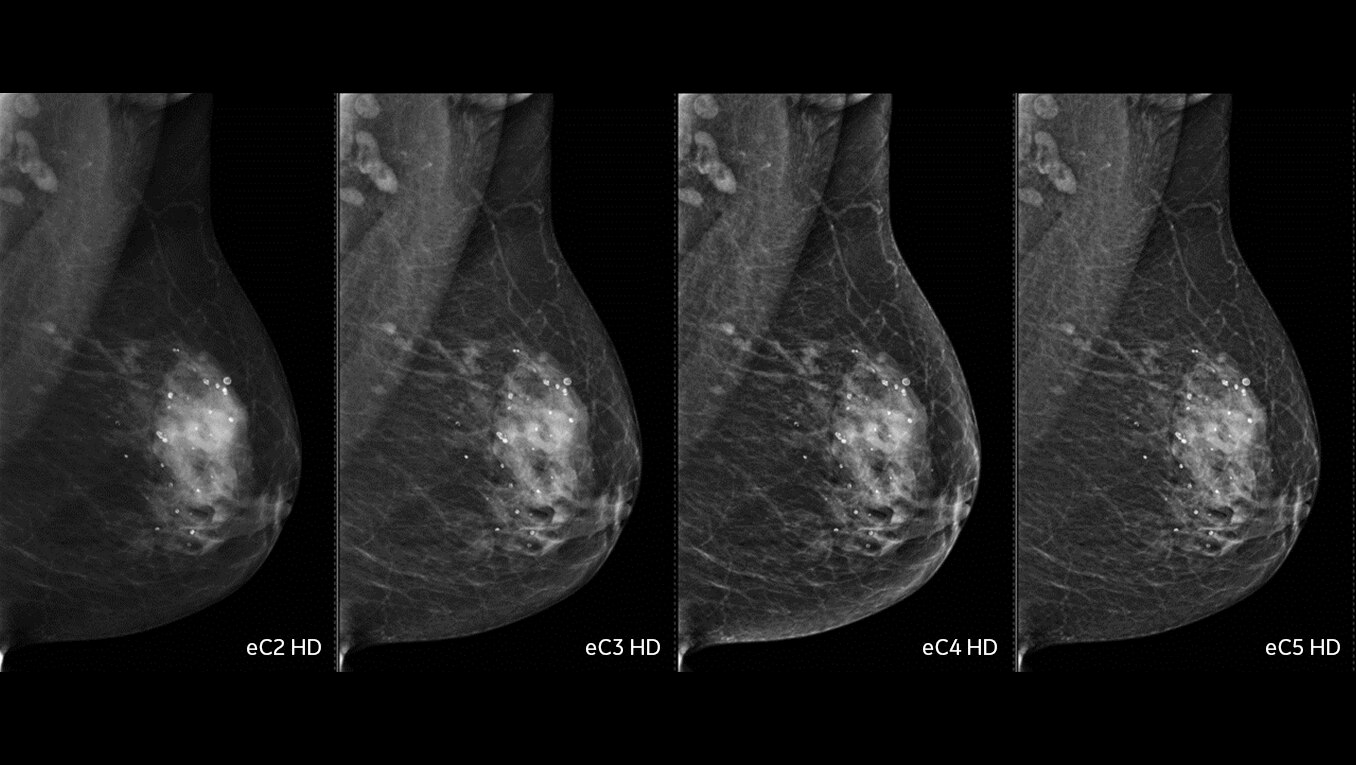

症例が複雑になれば、それだけ不確実な要素も伴います。だからこそ重要になるのは、いかに早期発見し、早期治療に専念できるかどうか。一手先を読み、よりよい未来を的確に見抜く先生方の日々の診断を、Voluson Expert 22の卓越した画質と独自のクリニカルツールがサポートします。

胎児心臓の異常を早期に検出することで、より迅速な介入、分娩計画、予後改善が見込まれます。Voluson Expert 22では、スクリーニング・診断・モニタリングまでトータルにサポートする多彩なツールを取り揃えています。